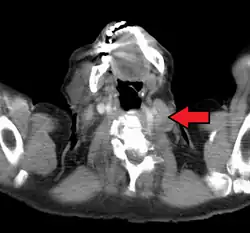

An enlarged Virchow's node as seen on CT

Malignancies of the internal organs can reach an advanced stage before giving symptoms. Stomach cancer, for example, can remain asymptomatic while metastasizing. One of the first visible spots where these tumors metastasize is one of the left supraclavicular lymph node.

Virchow's nodes take their supply from lymph vessels in the abdominal cavity, and are therefore sentinel lymph nodes of cancer in the abdomen, particularly gastric cancer, ovarian cancer, testicular cancer and kidney cancer, that has spread through the lymph vessels, and Hodgkin's lymphoma.[1] Such spread typically results in Troisier's sign, which is the finding of an enlarged, hard Virchow's node.[1]